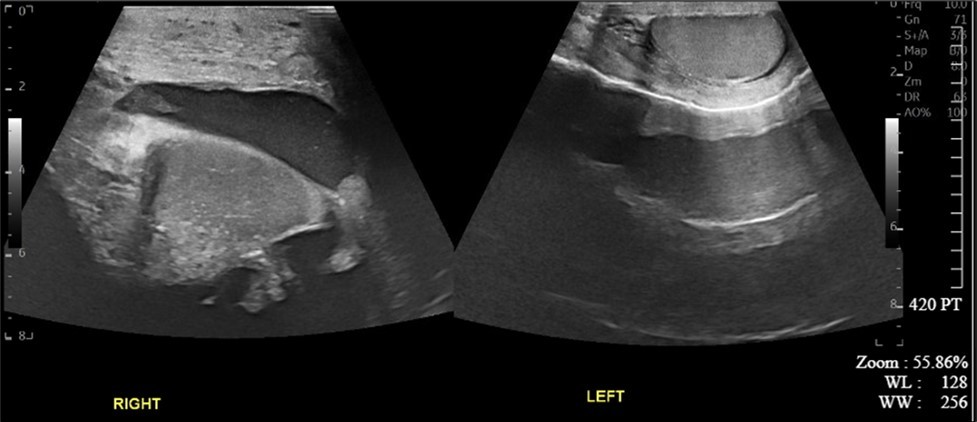

A 34-year-old male presented to the Emergency Department with complaints of large right-sided scrotal swelling, accompanied by scrotal discomfort. The patient’s past medical history was remarkable for a right-sided inguinal hernia, which had been present for several years and was repaired via right open herniorrhaphy with mesh placement three months prior. Physical examination prior to the herniorrhaphy revealed a large inguinoscrotal swelling, measuring 5 inches by 6 inches. During the herniorrhaphy, a very large hernia sac was encountered that could not be fully dissected from the cord structures and required placement of two large meshes; however, the testicles were successfully reduced back into the scrotum. Ultrasound of the right testicle revealed a large hypoechoic space with a complex collection and posterior displacement of the testicle, indicating a possible hydrocele (Figure 1, Figure 2, Figure 3, Figure 4). The patient was taken to the operating room for a right hydrocelectomy. During the procedure, it was noted that the penis was buried within the scrotal swelling, necessitating the placement of a Foley catheter to identify surrounding structures. Upon incision through the Dartos fascia, significant fibrotic tissue and fluid were encountered, making it difficult to maneuver around the hydrocele sac. Upon incising the hydrocele sac, a large collection of thick, dark brown fluid resembling old blood clots was immediately aspirated. Approximately 2 liters of fluid were drained from the sac. After identifying the testicle and cord structures, the proper placement of the testicle within the scrotum was verified. Due to excessive scrotal skin, a scrotoplasty was performed prior to suturing the scrotal skin and fascia (Figure 5). The postoperative hospital course was unremarkable. The patient was discharged with plans to return to the clinic for follow-up with the surgeon.

Figure 1.Ultrasound imaging of right and left testicles in the transverse plane.

Figure 2.Ultrasound imaging in the transverse plane of the right testicle.